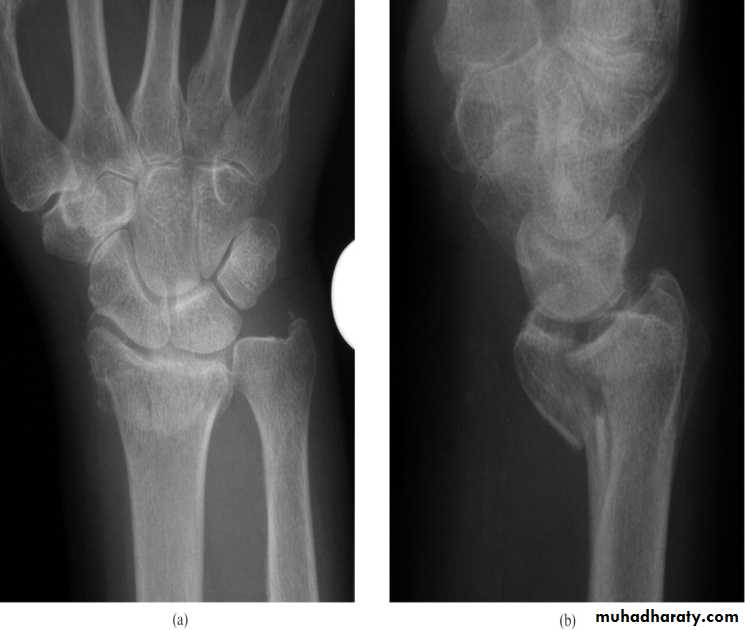

It is a transverse fracture of the distal end of the radius with posterior displacement of the distal fragment.

X-ray : there is transverse fracture of the radius at the cortico – cancellous junction , and the distal fragment is displaced posteriorly ; some time it is severely comminuted or crushed

It must be reduced under general anesthesia, the reduction will be by traction on the hand in the length of the bone , the distal fragment then pushed into place by pressing on the dorsum while manipulating the wrist into flexion , ulnar deviation and pronationThen put back slab and check by x-ray .